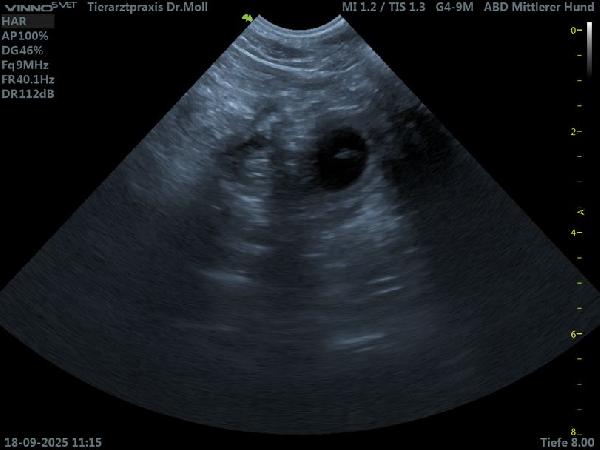

18.09.2025 - Hurra Queen Bee ist trächtig

R-Wurf04

Das erste Bild vom R-Wurf

Heute waren Queen Bee und ich zum Ultraschall in Netphen. Voller Spannung sind wir hingefahren. Eigentlich war der 21. Tag einer eventuellen Trächtigkeit ja noch ein bisschen früh, um ein Ultraschall zu machen, aber wir wollten ja noch nach Ostfriesland. Dr. Moll gab dich viel Mühe und dann konnten wir die beiden ersten Fruchtblasen erkennen. Meine Freude war riesig, ich glaube Queen Bee war es in dem Moment egal. Somit rechnen wir nun um den 30. Oktober mit kleinen Black Fellows.